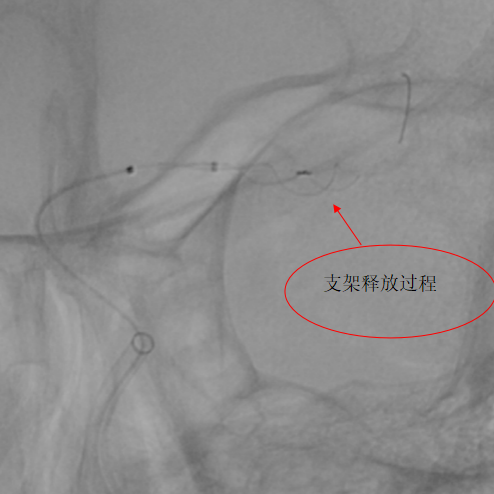

第二例患者为左侧大脑中动脉动脉瘤,该部位血管解剖结构复杂,对手术的精准度要求极高。团队使用血流导向装置,支架完美打开及贴壁,患者术后3天顺利出院。